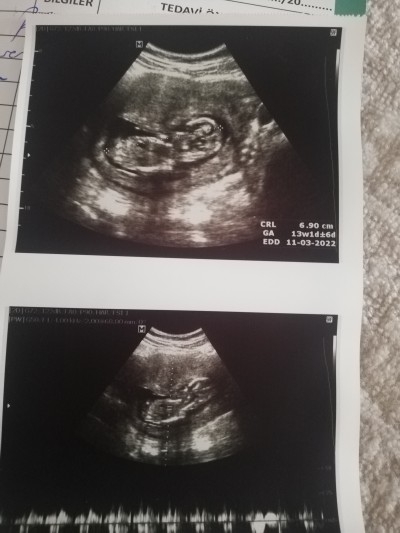

13 haftalığız nub teorisi ile bakacak olan var mı cinsiyete bakacak 2 fotoğraf var

image